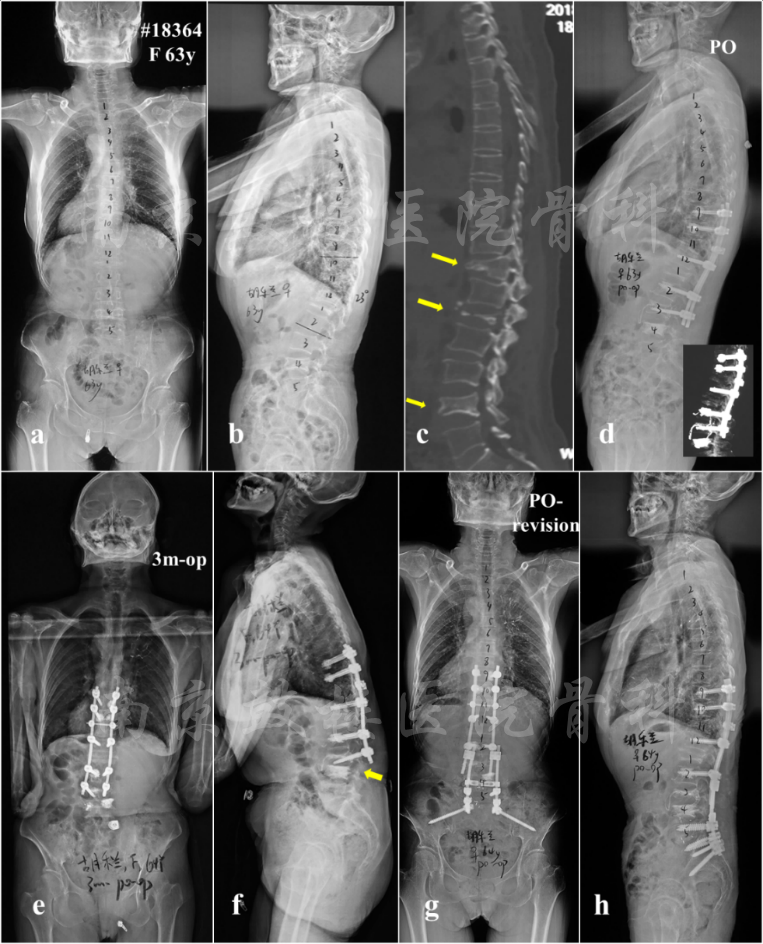

图2 女,63岁,多发骨质疏松性骨折(T11,L1,L4),类风关病史,长期服用激素(b, c);初次手术行骨折切开复位内固定(T9-L3),其中T9,T10,L2及L3均使用骨水泥螺钉加强,L4椎体行骨水泥注入(d);术后3个月出现远端交界性失败(DJK),L3螺钉拔出,矢状面躯干失平衡(e, f);行翻修术,将内固定延长至骨盆并使用S2AI螺钉固定,L4/5及L5/S1行TLIF支撑(g, h)